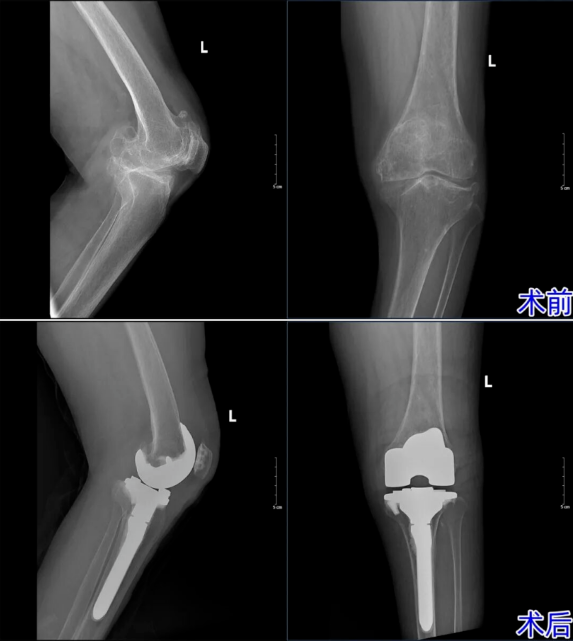

年轻时,双膝反复的酸痛便如影随形,其中右膝的症状尤为剧烈。直到2025年7月,持续的剧痛彻底击碎了老人的生活节奏——起身艰难、步态蹒跚,她才在家人的搀扶下,慕名来到济南南郊医院骨二科求医。经详细检查,结果令人揪心:王奶奶被确诊为双膝重度骨关节炎,且右膝病变已发展至终末期。杨学良主任团队迅速响应,为其成功实施了右膝关节置换术。术后,那纠缠多年的梦魇终于消散,关节屈伸恢复如常,王奶奶生平第一次体会到了“走路不疼”的轻松。

然而,左膝的隐患并未随之而去。随着疼痛日益加剧、关节严重变形,老人连基本的日常行走都举步维艰。“右腿好了,左腿绝不能拖后腿!”怀着对健康的渴望,王奶奶毫不犹豫地再次将信任交给了骨二科。面对左膝高达30°的内翻畸形、仅10°-100°的屈伸活动度,杨学良主任带领团队开启了新一轮的技术攻坚。从全面的心肺功能评估到假体的精确选型,从微创切口的设计到截骨角度的测算,每一个环节都精雕细琢,力求完美。